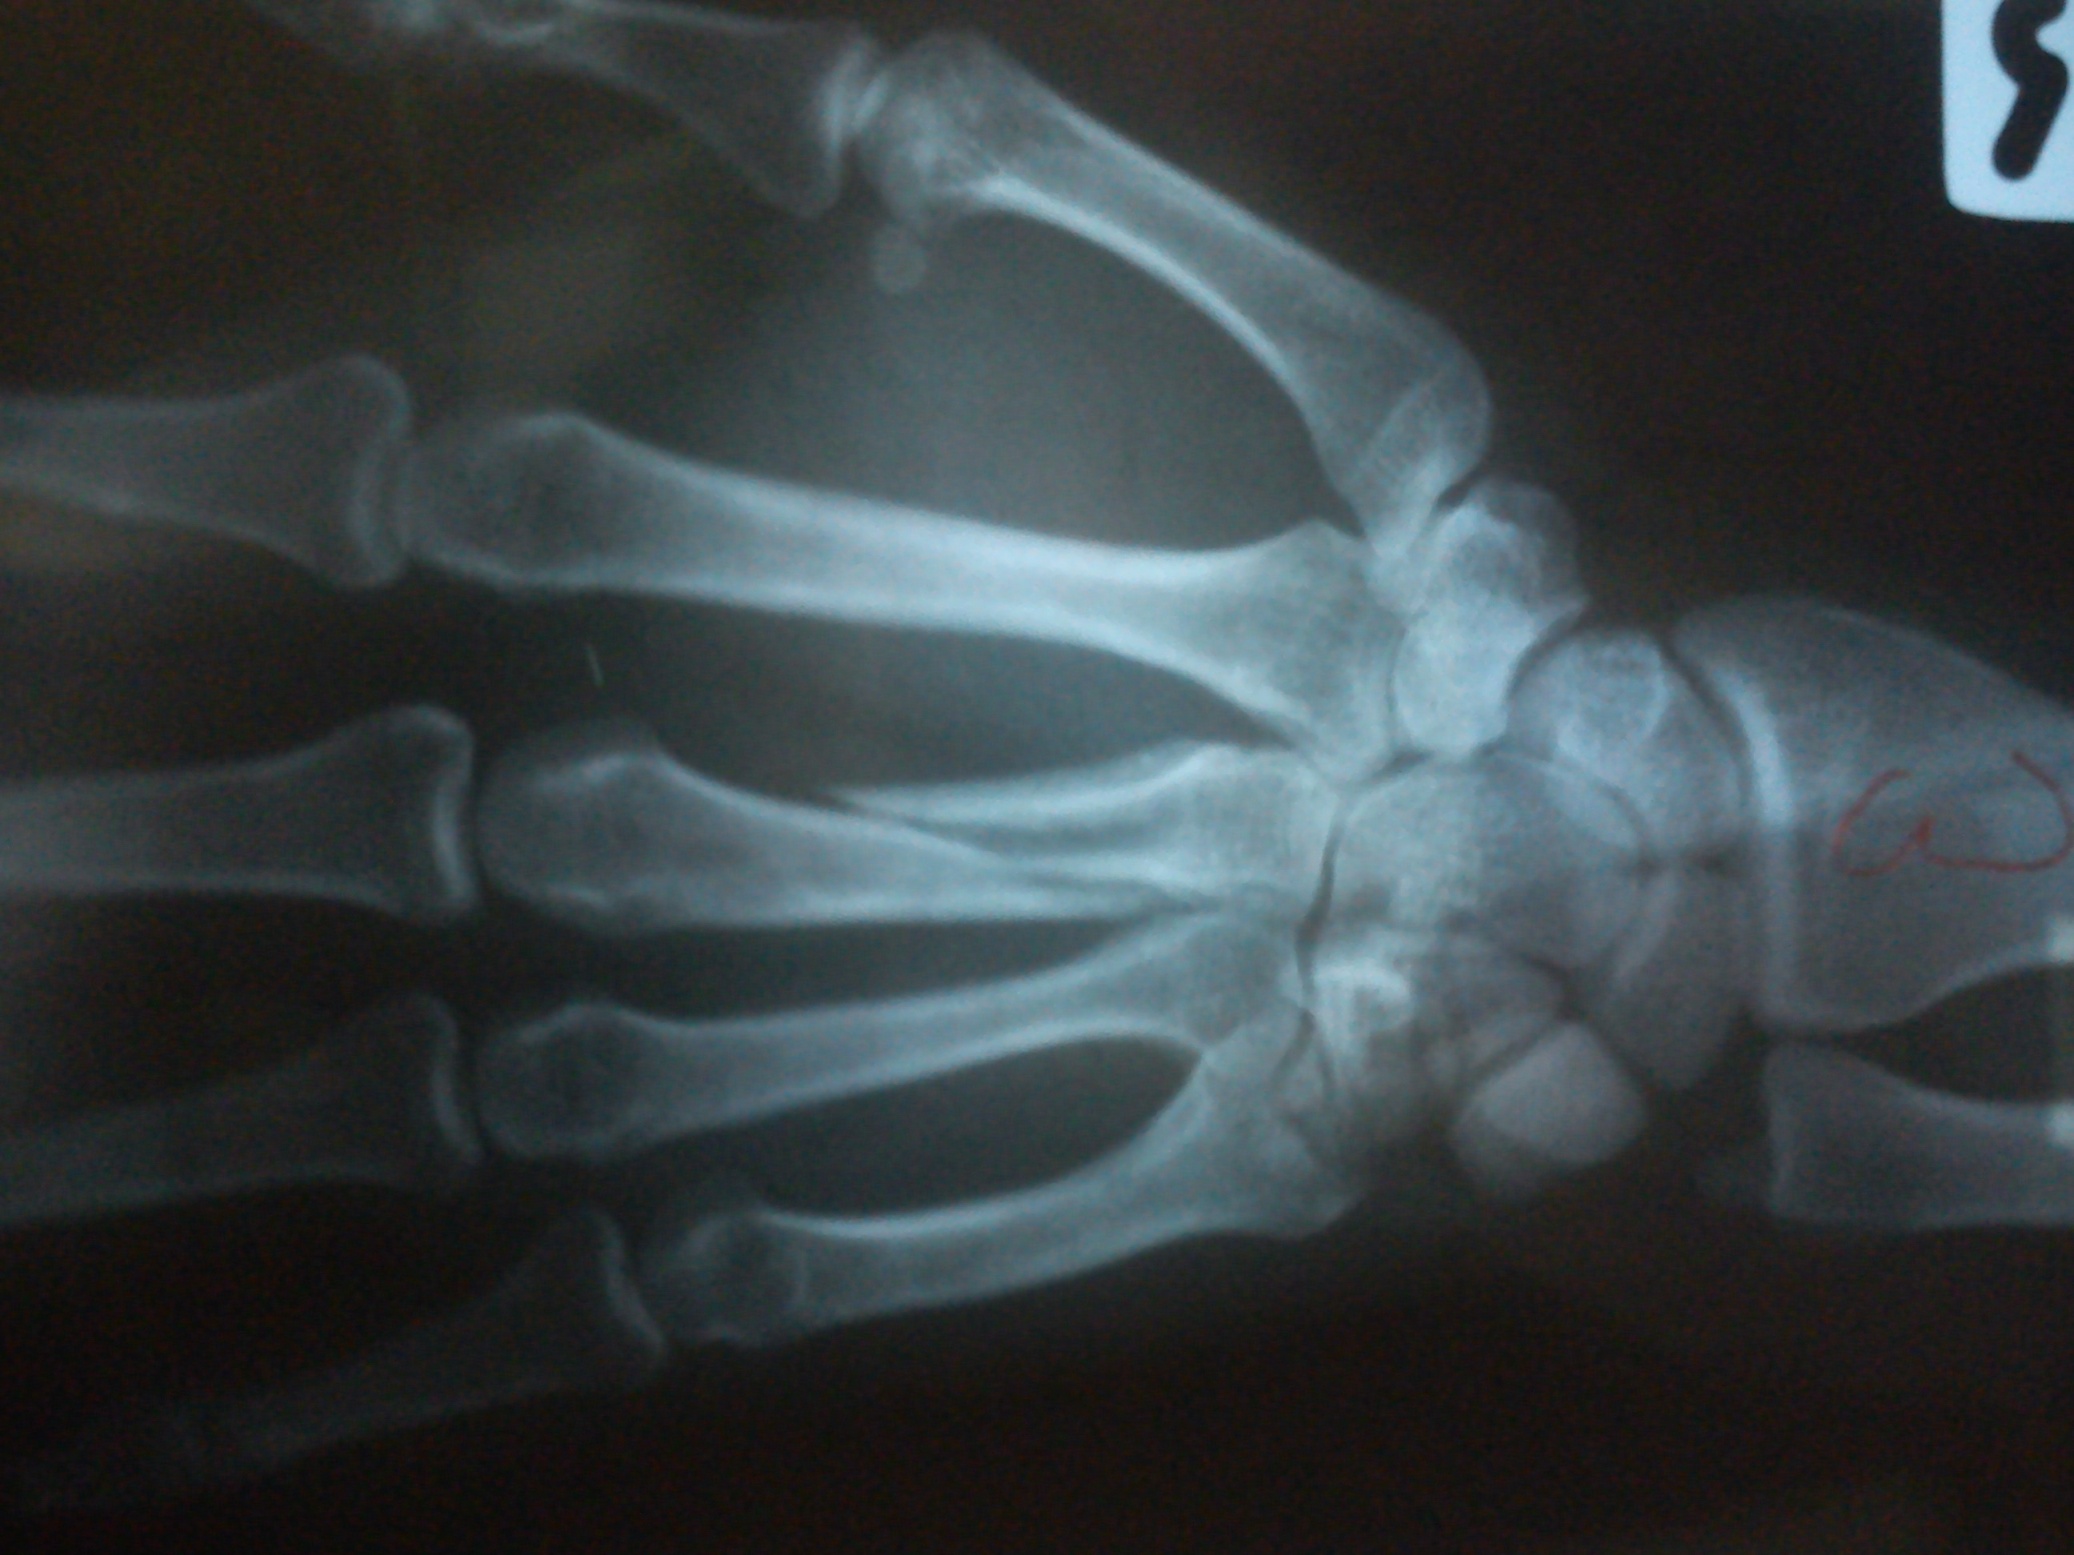

ปัญหา จะมี ๒ ประเด็นหลัก

๑. กระดูกนิ้ว สั้นลง

๒. กระดูกนิ้ว บิดหมุน

สิ่งที่จะตามมา ก็คือ กำมือไม่แน่น หรือ กำมือแล้วนิ้วจะซ้อนทับกัน ..

แต่การประเมินว่า ควรจะรักษาแบบไหน ก็ต้องอาศัยการตรวจร่างกาย และ ประเมินกิจกรรมการใช้งาน .. เช่น ถ้ามีอาชีพ นักเปียนโน .. แบบนี้ ก็ผ่าเลย เพราะ นิ้วสั้นลงไป ก็จะมีปัญหาในการเล่นเปียโน เป็นต้น

กระดูกมือหัก เชื่อมผิดรูป

เมื่อวานไปให้หมอที่โรงบาลเอกเรย์มา คุณหมอบอกว่ากระดูกมีรอยเชื่อมแล้ว

ก้อเลยให้เอาเฝือกออก ผมอยากรู้ว่ากระดูกมันเชื่อมผิดรุปแบบนี้ จะมีผลอะไรมั้ยคับ

คือตอนนี้ผมกำมือไม่สุดอ่ะคับ แล้วก็เสียวตรงกระดูกตลอดเลย